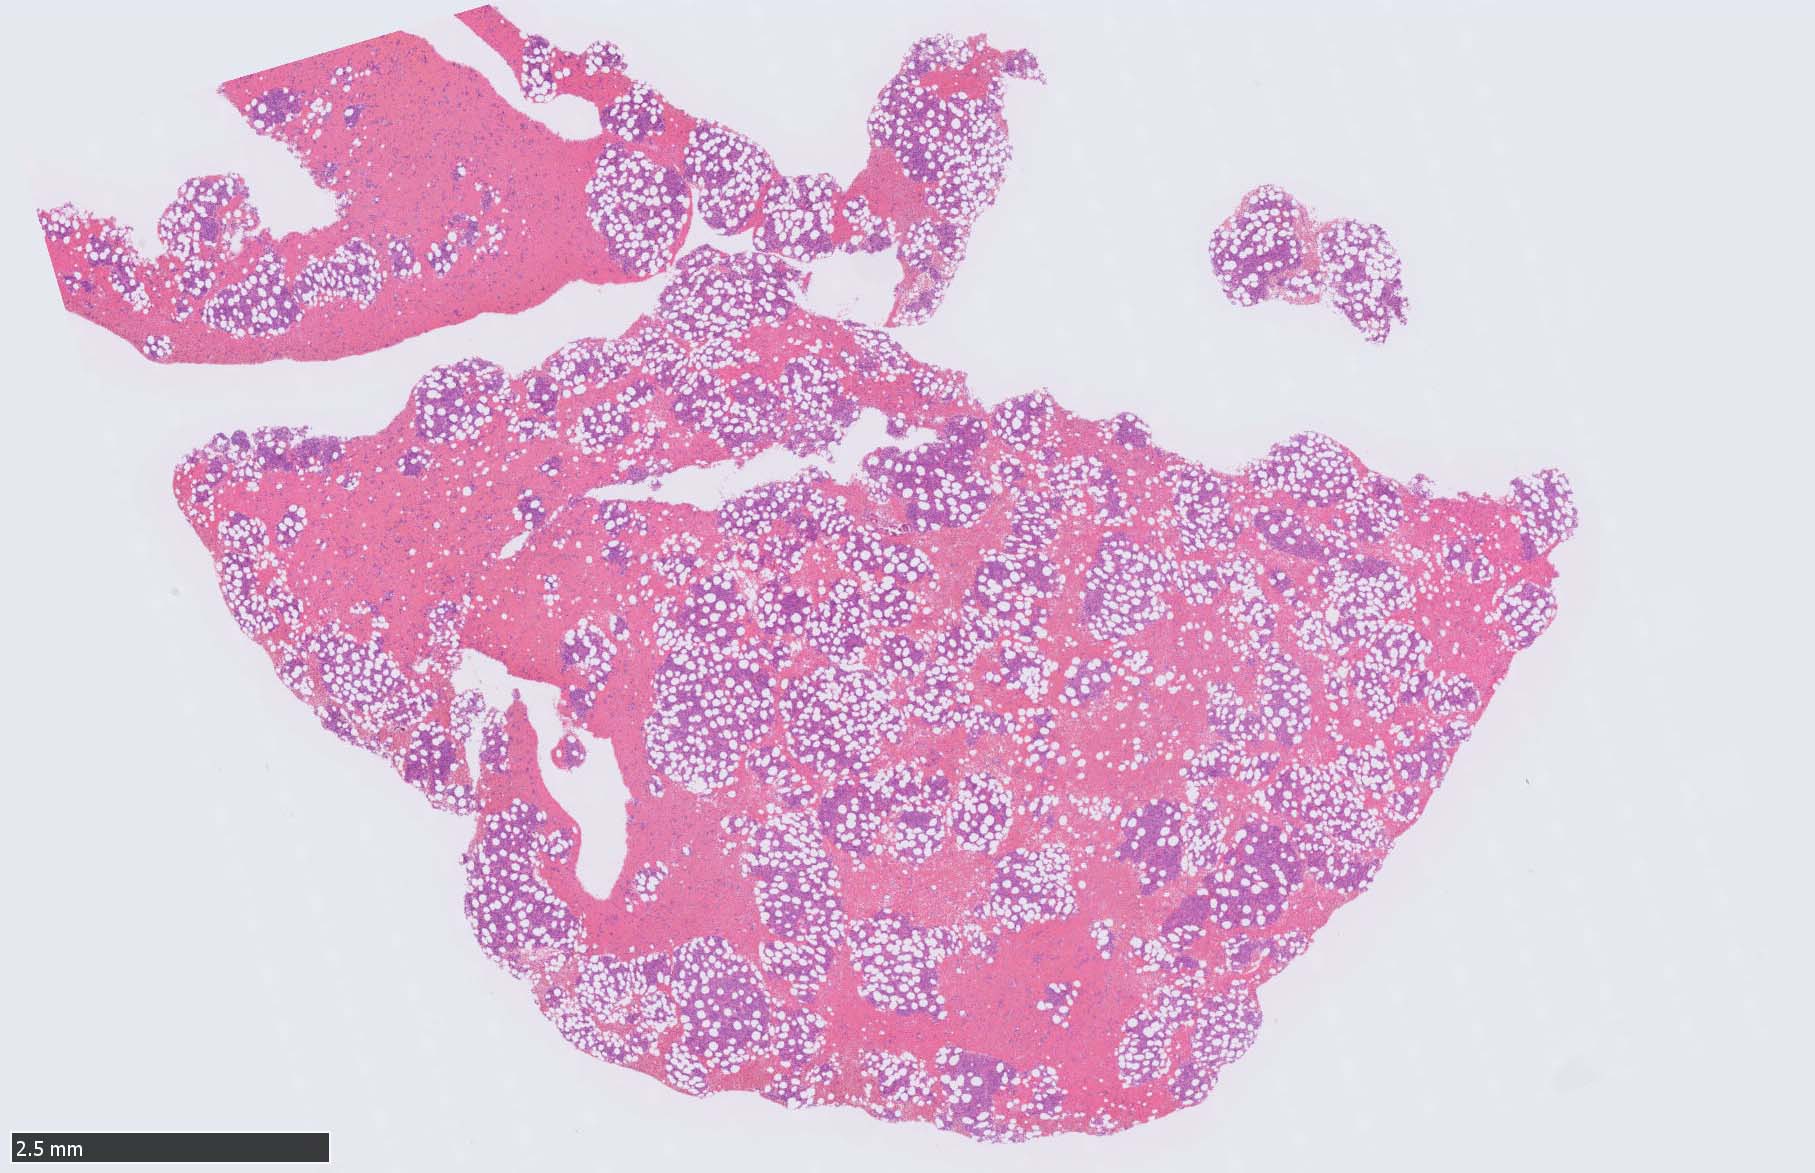

骨髄病理所見

HEでは腫瘍細胞の同定が難しい. 本症例は ASD-Giemsa染色を見ても, 腫瘍胞巣はよくわからなかった. 皮膚が先に診断がつき, 次いでBone marrowだったため, 免疫染色にすすめたが, Bone marrowが先だと診断に困ったかもしれない. 本例は, 骨髄がhypercellularで, dysplastic hematopoiesisがありMDSも疑われている.

BPDCN骨髄病変の病理

症例骨髄に認められた異形成造血所見

Mgkは低分葉, 円形単核の細胞が多く, 分離円形核のMgkもみられた. 赤芽球はproerythroblstsのみの小集簇や孤在性出現あり. 成熟赤芽球が乏しい. 顆粒球系細胞も分葉好中球への分化像が少ない.

免疫染色では, HbFを発現する赤芽球の集簇巣が散見しているほか, p53陽性細胞が軽度に増加している. CD34陽性細胞増加はなし.CD42b染色でmicroMgkはみられなかった. 異形成造血が強く疑われる.